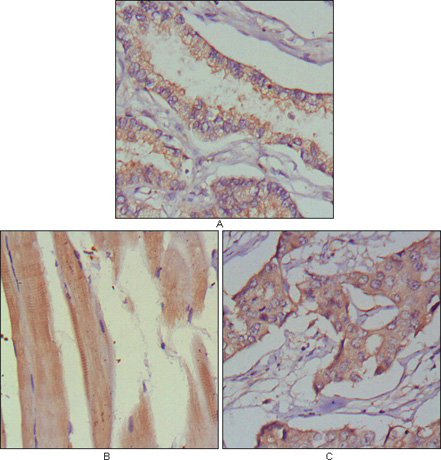

Figure 1: Immunohistochemical analysis of paraffin-embedded human lung cancer (A), muscles (B) and breast cancer (C) using MUSK mouse mAb with DAB staining. |